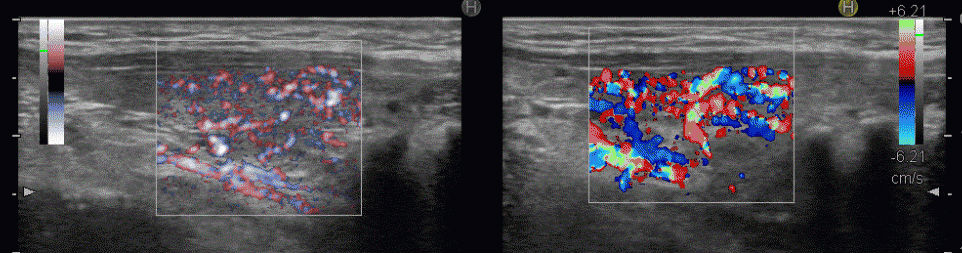

eFlow(イー フロー)と通常ドプラーの比較

(左)通常ドプラー;甲状腺内の血流のため、血管と周辺の甲状腺組織までが隠れてしまいます

(右) eFlow(イー フロー);甲状腺内の血管が鮮明に判ります

(左) eFlow(イー フロー);甲状腺内の血管が鮮明に判ります

(右) 通常ドプラー;甲状腺内の血流のため、血管と周辺の甲状腺組織までが隠れてしまいます

甲状腺機能亢進症/バセドウ病 eFlow(イー フロー)

(左) eFlow(イー フロー)(拡大);甲状腺内の血管が鮮明に判ります

(右) 通常ドプラー(拡大);甲状腺内の血流のため、血管と周辺の甲状腺組織までが隠れてしまいます